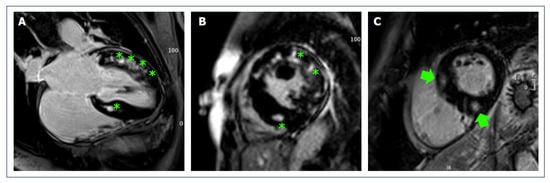

- Cipriani, A.; Mattesi, G.; Bariani, R.; Cecere, A.; Martini, N.; De Michieli, L.; Da Pozzo, S.; Corradin, S.; De Conti, G.; Zorzi, A.; et al. Cardiac magnetic resonance imaging of arrhythmogenic cardiomyopathy: Evolving diagnostic perspectives. Eur. Radiol. 2022, 32, 1–13. [Google Scholar] [CrossRef]

- Czimbalmos, C.; Csecs, I.; Dohy, Z.; Toth, A.; Suhai, F.I.; Müssigbrodt, A.; Kiss, O.; Geller, L.; Merkely, B.; Vago, H. Cardiac magnetic resonance based deformation imaging: Role of feature tracking in athletes with suspected arrhythmogenic right ventricular cardiomyopathy. Int. J. Cardiovasc. Imaging 2019, 35, 529–538. [Google Scholar] [CrossRef]